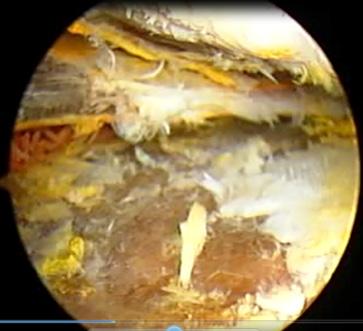

Embolización de la arteria genicular media para el tratamiento definitivo de los sangrados en las rodillas de pacientes hemofílicos. Por: Dr. Guillermo Capetillo Morales, Médico Traumatólogo Ortopedista. Pág. 118